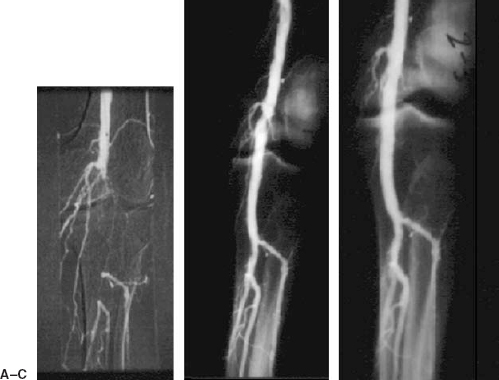

Percutaneous recanalization of total occlusions of the iliac vein ...